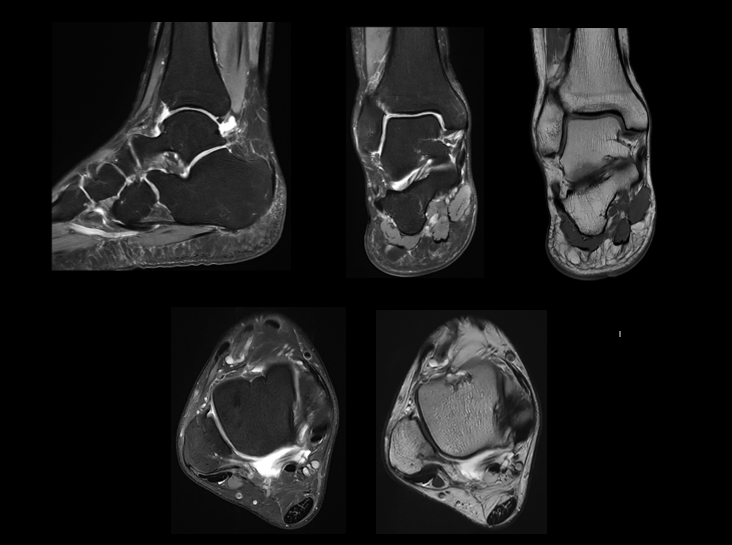

高分辨踝关节成像